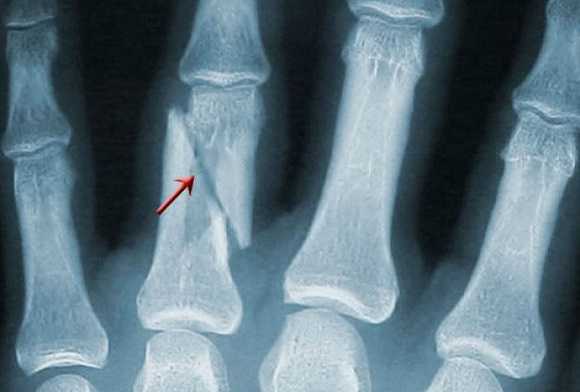

Снимки 11—V пальцев в прямой ладонной проекции .

Исследуемый палец укладывают ладонной поверхностью на неперекрытую половину кассеты размером 13X18 см. Пучок рентгеновского излучения направляют на проекцию проксимального межфалангового сустава (рис. 378).

На рентгенограмме видны фаланги и может быть частично видна I пястная кость, их медиальные и латеральные края, щели межфаланговых суставов (рис. 379).